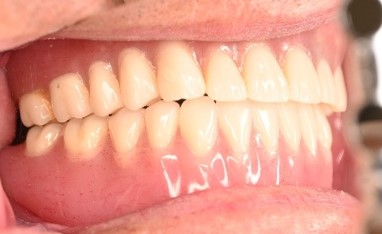

女性Tさん 50代(マグネット式入れ歯)

主訴

左上の犬歯が、グラグラして痛い

治療内容

他の歯も歯周病が進行していました。保存することができない歯が3本ありましたので、抜歯し、残った歯6本の歯周病治療をし、それらの歯を活用しマグネット式総入れ歯を入れました。

所感

マグネット式総入れ歯を活用し、もともとは反対交合でしたが、正常交合に改善することができました。

Before

赤丸は抜歯しました

After

【義歯を装着したところ】

【義歯を外したところ】

マグネット義歯

緑丸は組み込まれたマグネット